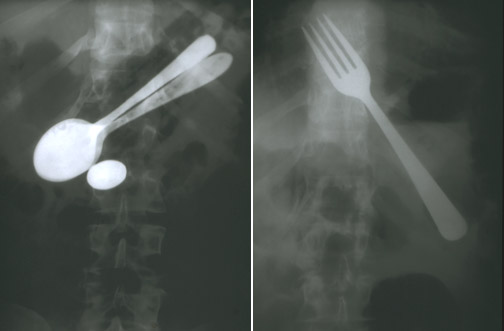

| The abdominal radiographs seen here are from the same patient, one year apart (the following year, a pen and pencil set was recovered, not the table knife that would have completed the set). A variety of foreign bodies may be swallowed, both willingly and involuntarily. Large objects may not pass the pylorus (such as these) requiring endoscopic removal. Small blunt objects may just pass through the GI tract. Sharp objects can perforate, necessitating surgery. |